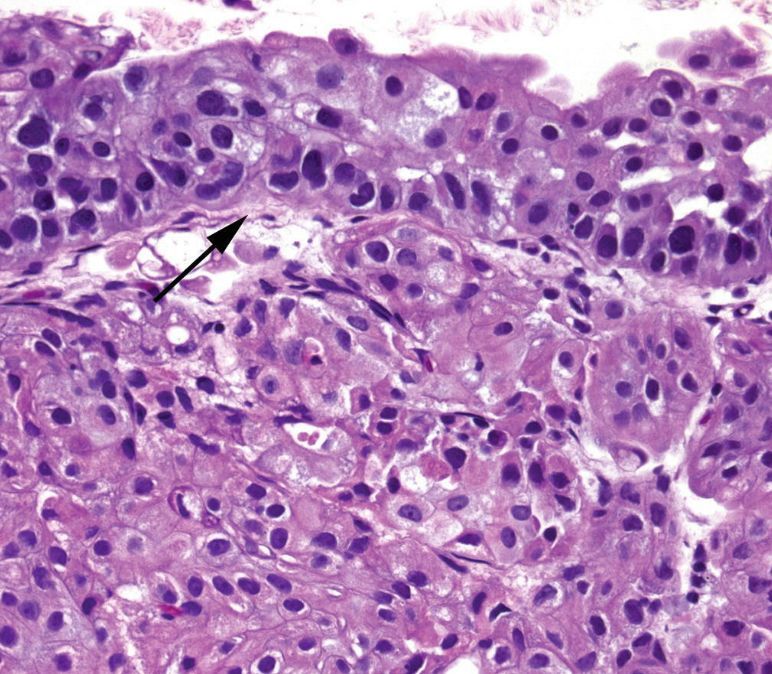

High grade papillary urothelial carcinoma

Papillary lesion lined by cells that look like CIS. May be noninvasive, but you have to look carefully for associated invasion (because it is often present!)

The urothelium is disordered with poor polarization. Nuclei are enlarged, hyperchromatic, and pleomorphic, maybe with nucleoli. Mitoses are seen at all levels of the epithelium and there is focal non-urothelial differentiation (squamous or glandular).